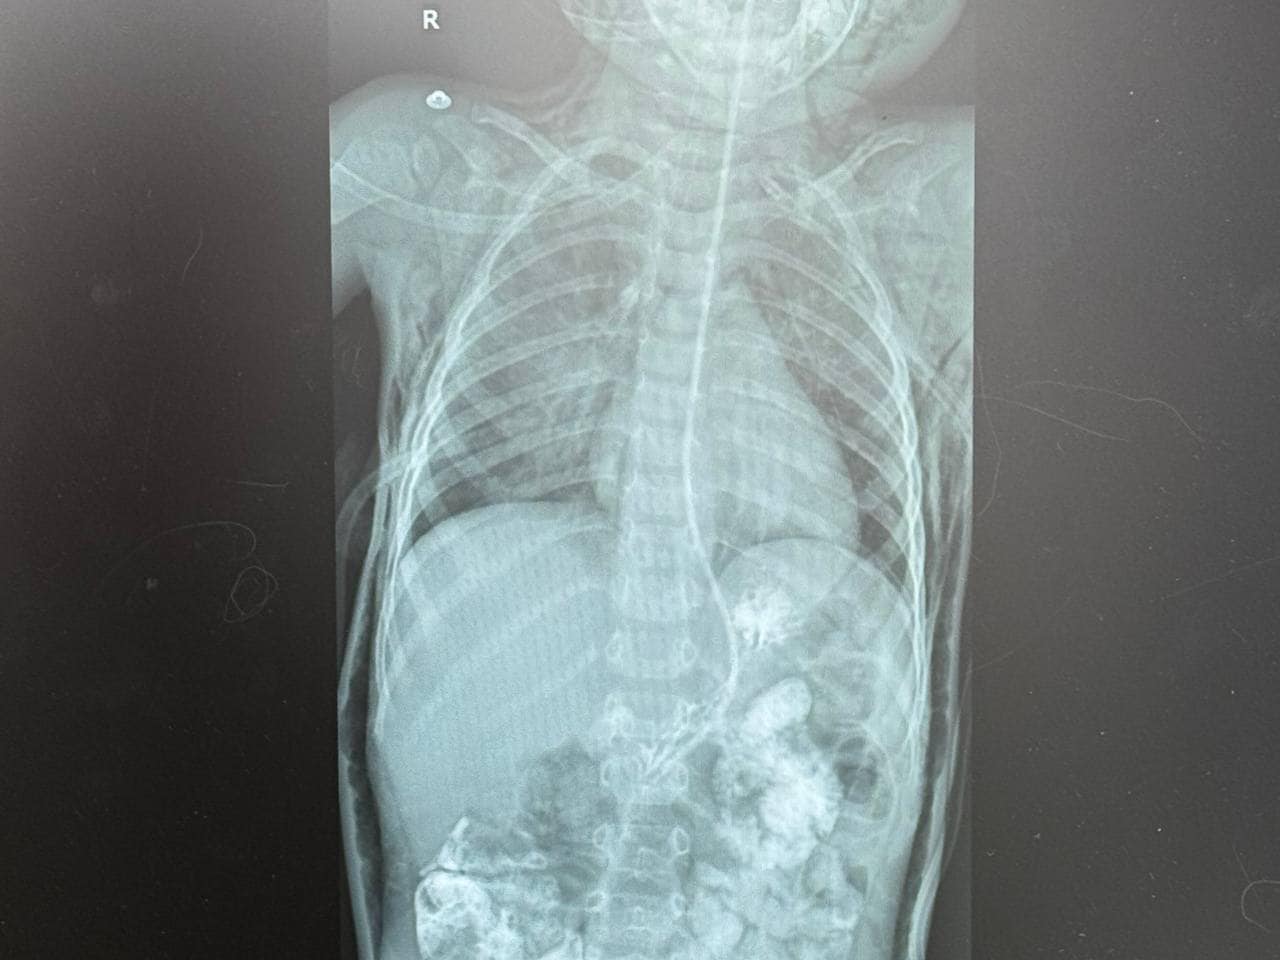

Після проведених рентгенівських обстежень та КТ лікарі виявили накопичення повітря в середостінні, під шкірою голови, шиї, грудної клітки. Це свідчило про порушену цілісність дихальних шляхів у хлопчика. Вже наступного дня Лука був терміново доставлений до «Охматдиту».У медзакладі команда спеціалістів оперативно зібралася для термінового обстеження та визначення плану подальших дій. Під час КТ, рентгенівських обстежень та бронхоскопії у дитини виявили розрив трахеї. Дефект був розташований на задній стінці трахеї, півтора сантиметра нижче голосових зв’язок. Довжина розриву становила 2,5-3 сантиметри.